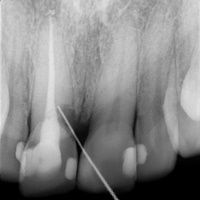

Wybielanie obejmujące pojedyncze zęby jest dość często spotykane. Najczęstszą przyczyną dyskoloracji zęba jest obumarcie miazgi i brak następowego poprawnego leczenia kanałowego, lub leczenie nieprawidłowe. Czasami udaje się przeprowadzić proces wybielania, który jest zadowalający dla pacjenta, a czasami w oparciu o uzyskany wynik można przeprowadzić leczenie protetyczne np. koroną lub licówką całoceramiczną.

Trzeba jednak uważać, ponieważ nieumiejętnie przeprowadzone wybielanie może być przyczyną resorpcji wewnętrznej i może sie skończyć utratą całego zęba...juz wybielonego. Poniżej zdjęcia przed i po leczeniu mikrochirurgicznym resorpcji.